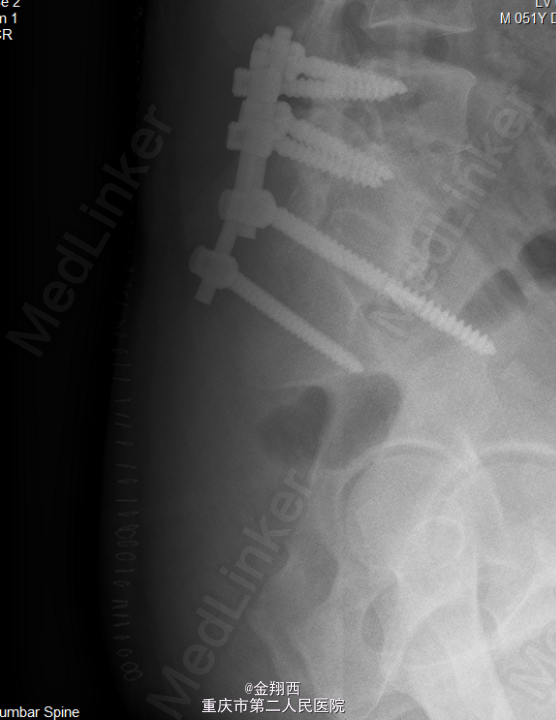

初步诊断:骶骨肿瘤。麻醉下行腹主动脉球囊阻断下骶骨肿瘤切除、内固定术。

术后输液改善循环,促进愈合治疗,定期换药后患者病情好转。术后病理提示(骶骨肿瘤穿刺活检)少量粘液样物质及成片上皮样细胞,免疫组化结果提示脊索瘤。免疫组化结果:S-100 部分+,CK(AE1/AE3) +,CAM5.2 +,EMA +,Vimentin +,Ki-67 5%+,P53 弱+,SMA -,calponin -,Desmin -。